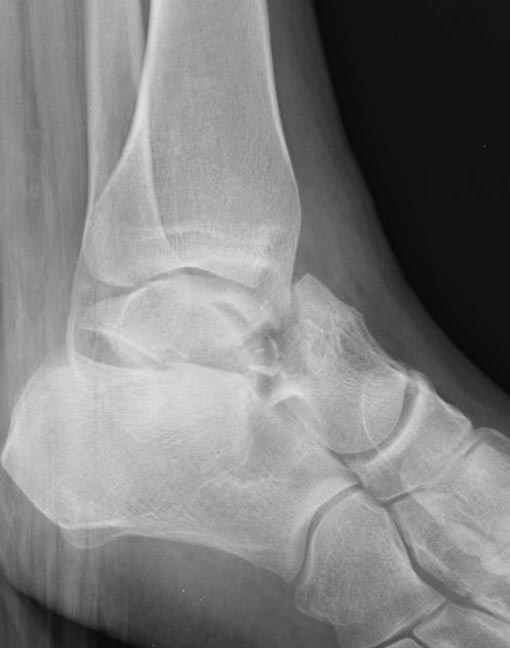

Уважаемые участники русского Ортофорума, поздравляю всех со всеми прошедшими праздниками: Новым годом, Рождеством, Hanukkah, Kwanzaa, желаю участникам всего наилучшего и здоровья.Повреждение таранной кости.Больной 81г автоавария, повреждение таранной кости, здесь снимки. Какие рекомендации?Djoldas Kuldjanov, MDDepartment of Orthopedic SurgerySt. Louis University Medical Center

Вообще то мало данных: торчит ли осколок под кожей, сопутствующая паталогия (атеросклероз, диабет), сколько времени прошло после травмы? Я думаю, что в данном случае можно ограничиться или небольшим вмешательством вплоть до удаления дистального отломка из небольшого разреза, или наложением аппарата с дистракцией переднего отдела стопы в эквинусе, может быть удастся этот отломок и вправить. Опорная функция в любом случае должна сохраниться при любом варианте лечения, не думаю что будет страдать кровоснабжение таранной кости. Я когда то удалил дистальную половину таранной кости, с последующим анкилозированием в тарано-ладьевидном суставе, хотя более опытные товарищи советовали провести астрагалэктомию, но тем не менее тогда результат оказался хороший. Конечно объязательно назначение препаратов улучшающих микроциркуляцию, противоотечная терапия и т.п. Удачи.

Вдогонку по поводу перелома таранной кости, больная 81, не страдает диабетом, перелом закрытый, в первый же день поступления ограничились временным наружным фиксатором (как на снимке).

Планировалась открытая фиксация после спадения отека, но больная пожелала лечиться по месту жительству в другом штате..